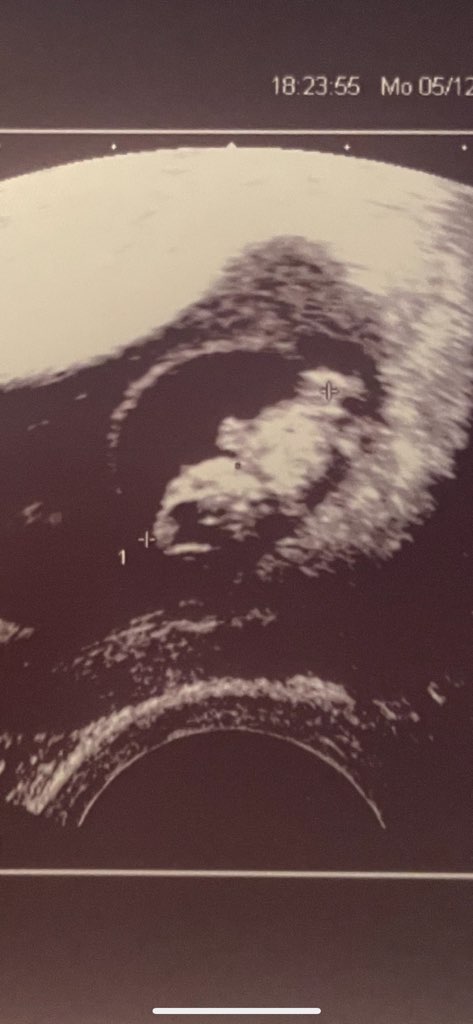

Ja dziś miałam wizytę, jestem 8+5. ostatnia wizyta była 15.11, na której było widać jakąś małą fasolkę przyklejoną do pęcherzyk, a dziś zobaczyłam serduszko jak bije (lekarz nie włączał dźwięku, nawet nie pytałam ani nic), po prostu poprosiłam żeby mi przybliżył j pokazał dokładnie ten punkcik 😍

W czwartek mamy wizytę prywatna na 9:00 wiec mysle, ze ten lekarz już więcej powie, bo ten z dzisiaj jest generalnie taki bardzo wyluzowany, może nawet za bardzo 🤷🏽‍♀️